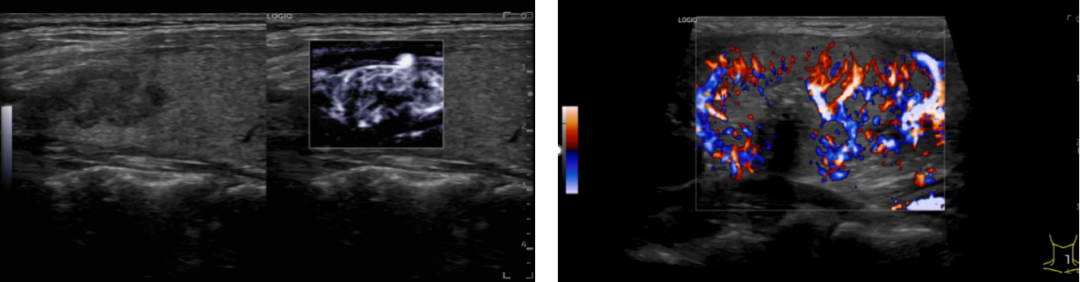

穿透力更强,分辨更精准

冰晶探头技术可在获得更高分辨力的同时兼顾高穿透力,帮助医师及时观察到脏器的病变。设备搭配的B-Flow™ 类造影血流和MVI 超微细血流成像,对血流显示能力大幅提升, 可捕捉到组织及病灶的细小血管,可观察到血管中较小斑块,提高临床诊疗能力。同时配备应力式弹性成像,对一些器官的结节,可做弹性成像检查,进一步明确肿物性质。

▲新的血流成像技术可清晰包络出甲状腺结节隐藏边界&甲状腺结节内丰富的血流